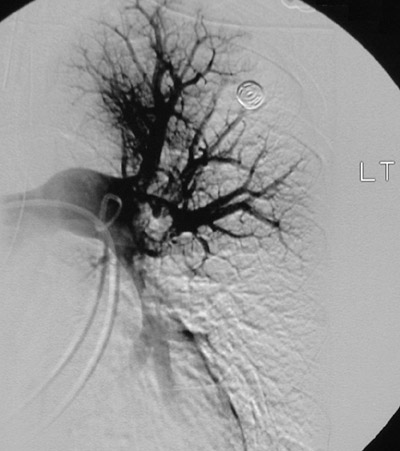

These views follow thrombolysis with an angiogram in a patient with multiple pulmonary thromboemboli. Note that there is increased filling compared to the prior set of images. There is still some delay in filling

toward the lower lung

.